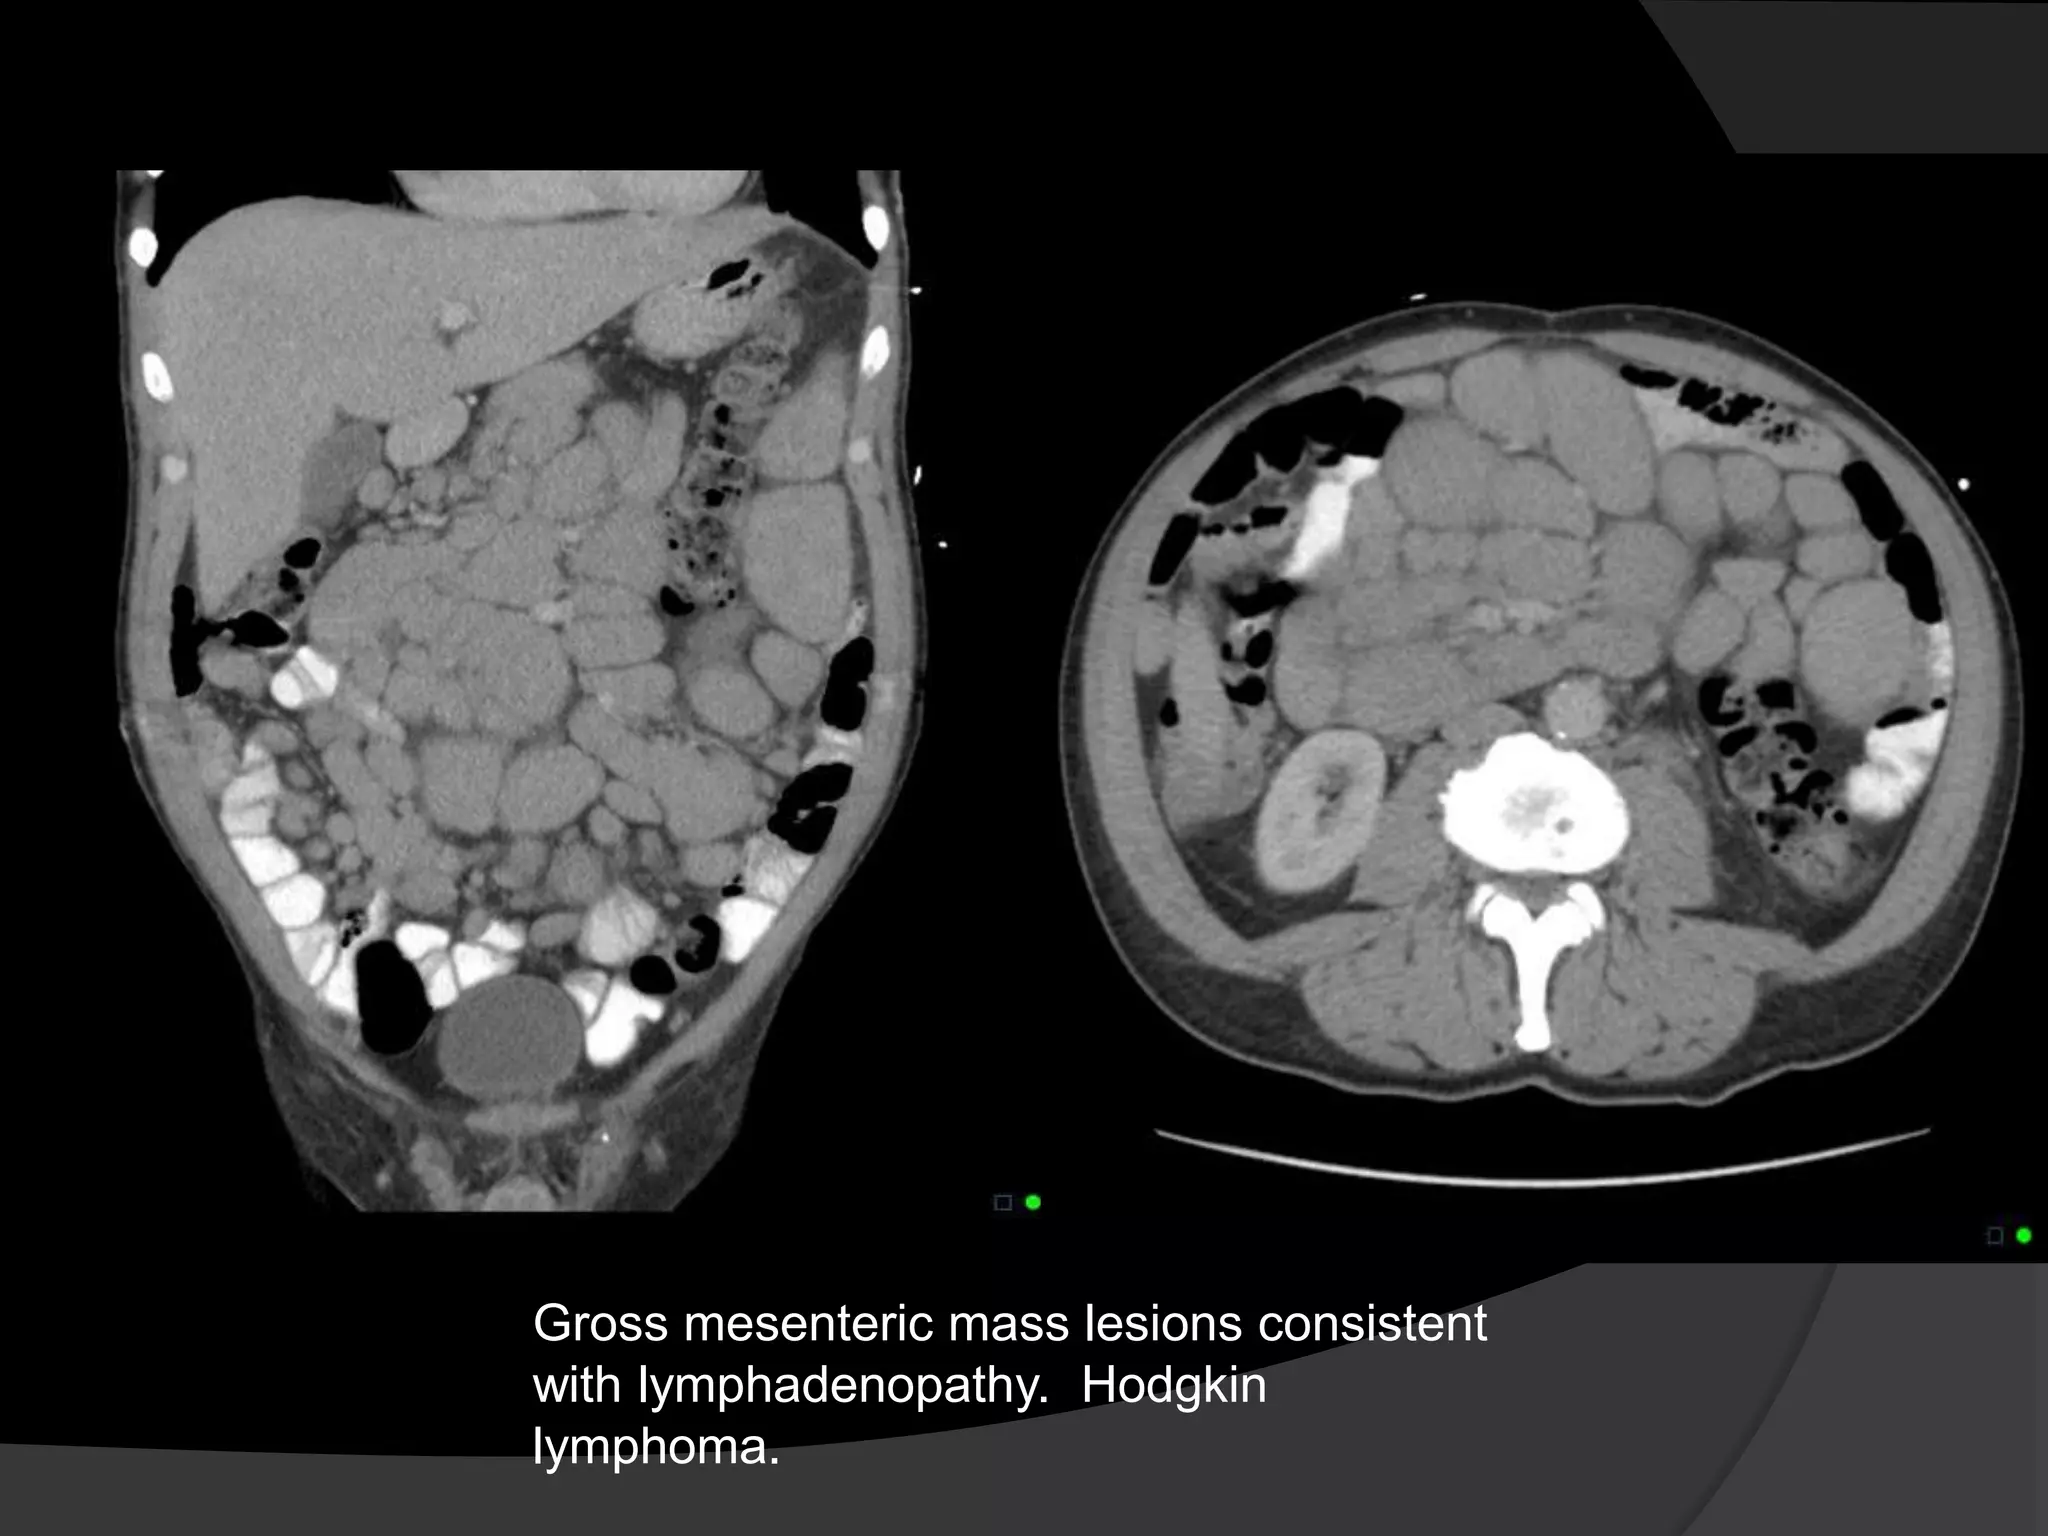

Gross mesenteric mass lesions consistent

with lymphadenopathy. Hodgkin

lymphoma.